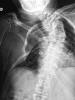

APR Gonartrosis

ACT Osteonecrosis de rodilla, fase 3.

ACT Osteonecrosis de rodilla , fase 2.